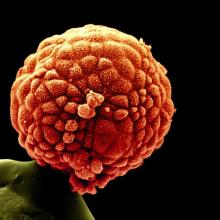

Embryonic stem cell research: an ethical dilemma